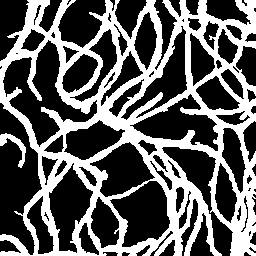

Semantic segmentation of blood vessels is an important task in medical image analysis, but its progress is often hindered by the scarcity of large annotated datasets and the poor generalization of models across different imaging modalities. A key aspect is the tendency of Convolutional Neural Networks (CNNs) to learn texture-based features, which limits their performance when applied to new domains with different visual characteristics. We hypothesize that leveraging geometric priors of vessel shapes, such as their tubular and branching nature, can lead to more robust and data-efficient models. To investigate this, we introduce VessShape, a methodology for generating large-scale 2D synthetic datasets designed to instill a shape bias in segmentation models. VessShape images contain procedurally generated tubular geometries combined with a wide variety of foreground and background textures, encouraging models to learn shape cues rather than textures. We demonstrate that a model pre-trained on VessShape images achieves strong few-shot segmentation performance on two real-world datasets from different domains, requiring only four to ten samples for fine-tuning. Furthermore, the model exhibits notable zero-shot capabilities, effectively segmenting vessels in unseen domains without any target-specific training. Our results indicate that pre-training with a strong shape bias can be an effective strategy to overcome data scarcity and improve model generalization in blood vessel segmentation.